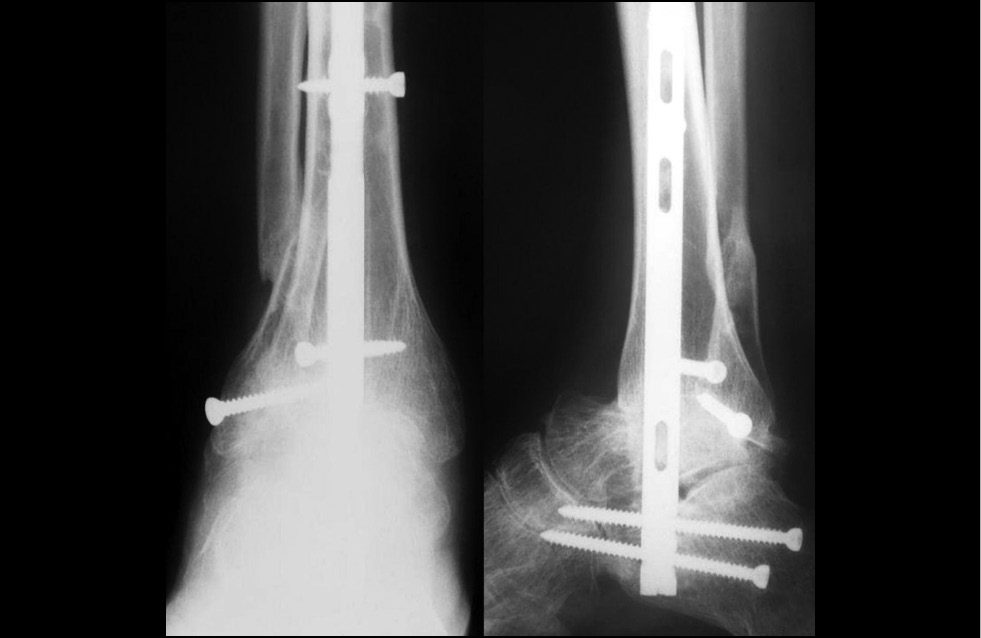

Рис. 2. Рентгенограммы, фиксирующие порочное положение стоп и голеностопных суставов, остеопороз, подвывихи в таранно-ладьевидных суставах

Fig. 2. Radiographs presenting the vicious position of feet and ankle joints, osteoporosis, talonavicular joints subluxation

Рис. 5. Послеоперационная рентгенограмма правой стопы и голеностопного сустава, стопа стала нагружаемой в правильном положении с распределением нагрузки на всю подошвенную поверхность

Fig. 5. Postoperative X-ray of the right foot and ankle, the foot became loaded in the correct position with the load distributed over the entire plantar surface